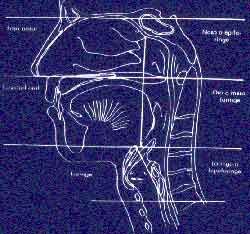

Como consecuencia del proceso antropológico las estructuras maxilofaciales quedaron agrupadas en tres zonas morfológicas diferentes: la cavidad bucal, la nasal y la faringea, siendo esta ultima el camino común para la entrada del aire y de los alimentos.

Como consecuencia del proceso antropológico las estructuras maxilofaciales quedaron agrupadas en tres zonas morfológicas diferentes: la cavidad bucal, la nasal y la faringea, siendo esta ultima el camino común para la entrada del aire y de los alimentos.

Sin embargo, los alimentos pasan al esófago y el aire a la traquea, pues la úvula, las fauces y la epiglotis están provistas de músculos constrictores, llamados cortinas, que sincronizan las funciones del aparato respiratorio y digestivo permitiendo que el alimento y el aire se entrecrucen en dirección dorso-ventral.

Esta disposición anatómica es la que facilita que sean las mismas estructuras, agrupadas en diferentes secuencias de movimientos elementales, las que participen en la realización de las diferentes praxias y que estas en su conjunto ejerzan una acción morfogénica sobre el crecimiento cráneo-facial.